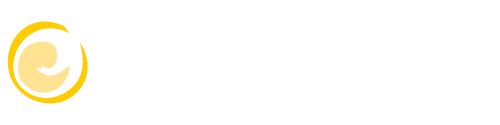

Das Angebot der erweiterten pränatalen Diagnostik in unserer Praxis erstreckt sich vom erweiterten Erst-Trimester-Screening mit Nackentransparenzmessung (lizenziert durch die FMF-London) und Hormondiagnostik (PAPP-A, f. ß-HCG), frühem Organultraschall und fetaler Echokardiographie, über die Feindiagnostik/Organultraschall im zweiten Trimester mit fetaler Echokardiographie und farbcodierter Doppleruntersuchungen bis hin zur invasiven Diagnostik mit Chorionzottenbiopsie (Mutterkuchenbiopsie) und Amniocentese (Fruchtwasserpunktion).

Erst-Trimester-Screening mit Nackentransparenzmessung um die 13.-14. Woche

Mit dem Voluson E10 ® von GE steht uns ein modernes Hochleistungs-Ultraschallgerät zur Verfügung.

Das Voluson E10 ®, ein Produkt der GE-Expert-Serie, wurde speziell für die fortschrittliche und subtile Feindiagnostik in Gynäkologie und Pränatalmedizin entwickelt. Wo komplexe Fälle nicht die Ausnahme, sondern die Regel sind. Wo schwierige diagnostische Fragen tagtäglich zu lösen sind. Wo Patienten eine umfassende Information und Beratung erwarten.